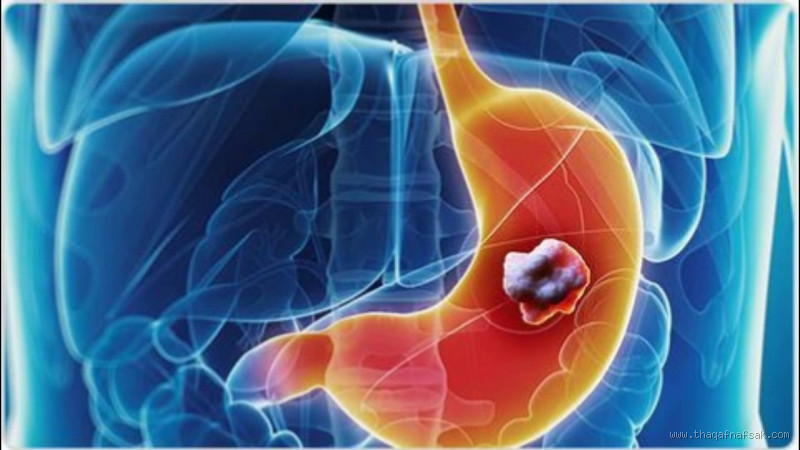

سرطان المعدة هو أحد أنواع السرطان التي تبدأ في معدة الإنسان، وهي عضو مهم في جهاز الهضم. هذا النوع من السرطان يمكن أن يسبب العديد من الأعراض المزعجة، مثل الألم في المعدة، والغثيان، وفقدان الوزن غير المبرر. لكن، هل ينتشر سرطان المعدة بسرعة؟ هذا هو السؤال الذي يشغل بال العديد من الأشخاص الذين يعانون من هذا المرض أو ممن لديهم مخاوف بشأنه.

قبل أن نتطرق للإجابة عن هذا السؤال، من المهم معرفة أن سرطان المعدة يمكن أن يأتي بعدة أنواع. أبرزها هو سرطان الغدة المعدية، الذي يحدث عندما تنمو الخلايا السرطانية في الغشاء المخاطي للمعدة. كما يمكن أن يتطور السرطان إلى أجزاء أخرى من الجهاز الهضمي أو أعضاء مجاورة إذا لم يتم اكتشافه وعلاجه مبكرًا.

السرطان بشكل عام هو حالة تنمو فيها خلايا غير طبيعية وتنقسم بسرعة. لكن عندما نتحدث عن سرطان المعدة، فهناك عوامل معينة تحدد مدى سرعة انتشاره.

في معظم الحالات، سرطان المعدة ينتقل أولاً عبر الجهاز اللمفاوي، الذي يشمل الغدد اللمفاوية الموجودة في البطن. يمكن أن يصل السرطان من المعدة إلى الغدد اللمفاوية القريبة، وبعدها يمكن أن ينتقل إلى الأعضاء البعيدة مثل الكبد أو الرئتين. أذكر أنني تحدثت مع صديقي خالد الذي كان يعاني من سرطان المعدة، وقال لي أنه في البداية، لم يكن يعتقد أن السرطان سيصل إلى أعضاء أخرى بسرعة، لكن تبين أن الانتشار عن طريق الجهاز اللمفاوي كان أسرع مما توقع.

في بعض الحالات، قد يصل سرطان المعدة إلى الأعضاء البعيدة عن طريق الدم. يحدث هذا عندما تدخل الخلايا السرطانية إلى مجرى الدم وتنتقل إلى أماكن مثل الكبد أو الرئتين أو حتى العظام. هذا النوع من الانتشار يمكن أن يكون أكثر تعقيدًا في العلاج ويجعل المرض أكثر خطورة.